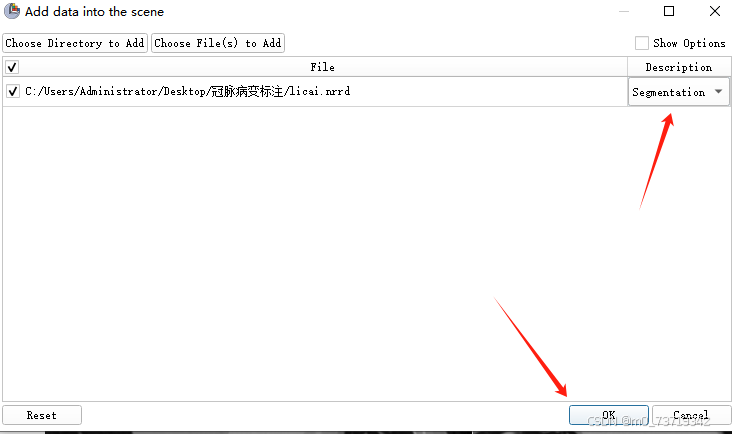

病人dicom数据导入同1,.nrrd数据导入如下